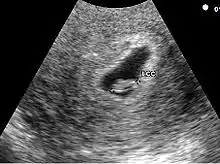

Embryon à 5 semaines

L'embryon est visible dès 5 semaines en cas d'utilisation de sonde endovaginale de haute fréquence. Il se présente comme une zone hyperéchogène coincée entre la vésicule vitelline et la paroi du sac ovulaire. Une activité cardiaque peut être visualisée. Il est déconseillé, à ce stade, d'utiliser le doppler pour entendre l'activité cardiaque embryonnaire en raison d'effet délétère possible sur la formation du cœur. En raison de la sensibilité humaine au mouvement, il est parfois possible de visualiser une activité cardiaque avant la visualisation de l'embryon. En pratique, l'activité cardiaque doit être systématiquement vue dès que l'embryon mesure 5 mm.

Embryon à 6 semaines

La croissance exponentielle de l'embryon permet très rapidement de le voir. Dès la visualisation de l'embryon une datation précise de la grossesse est possible. En cas de la visualisation de 2 sacs et / ou de 2 embryons, il est impératif de déterminer le type de grossesses gémellaires. Deux situations se rencontrent: